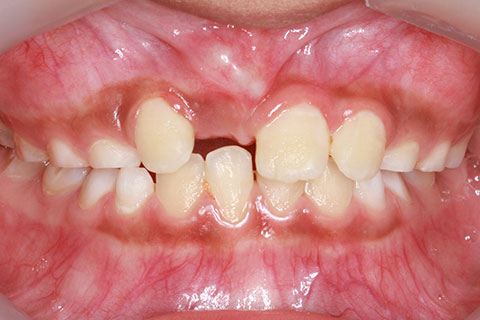

治療前

子供の乳歯が抜けて、かなりの時間が経つのに永久歯が生えてこないと心配して来院される親御様は多くいらっしゃいます。この場合、レントゲンにて確認すると大体の場合、もうしばらく待っていれば生えてくるであろうと予測がつきます。しかし、稀に歯の位置異常により、埋まったままの状態で生えてこないことがあります。この場合、待っていても生えてきませんので、矯正力により歯を引っ張り出す必要があります。これを矯正学では開窓・牽引術と呼び、歯肉を切開して、歯の表面を露出させ、そこに矯正器具を付けて、良好な位置まで引っ張り出すという治療法です。